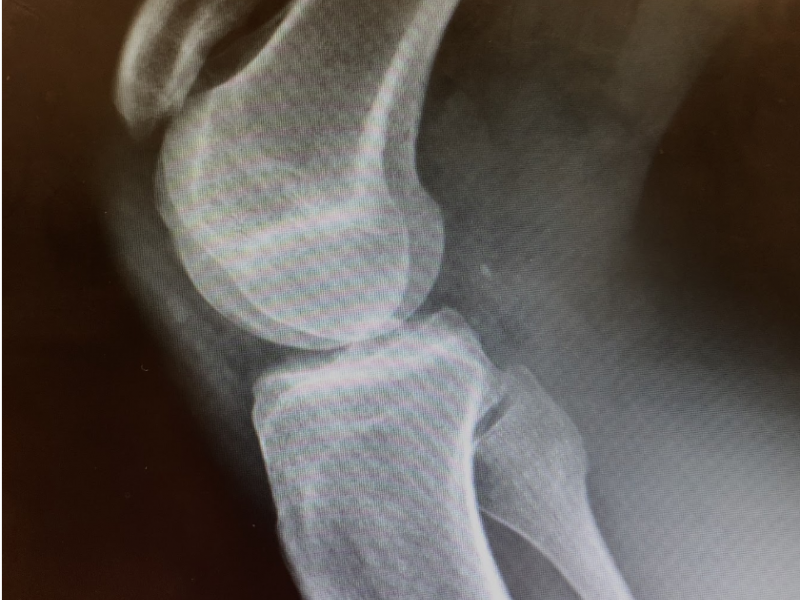

Back to Basics: A Case of Traumatic Knee Pain By Dr. Ozair